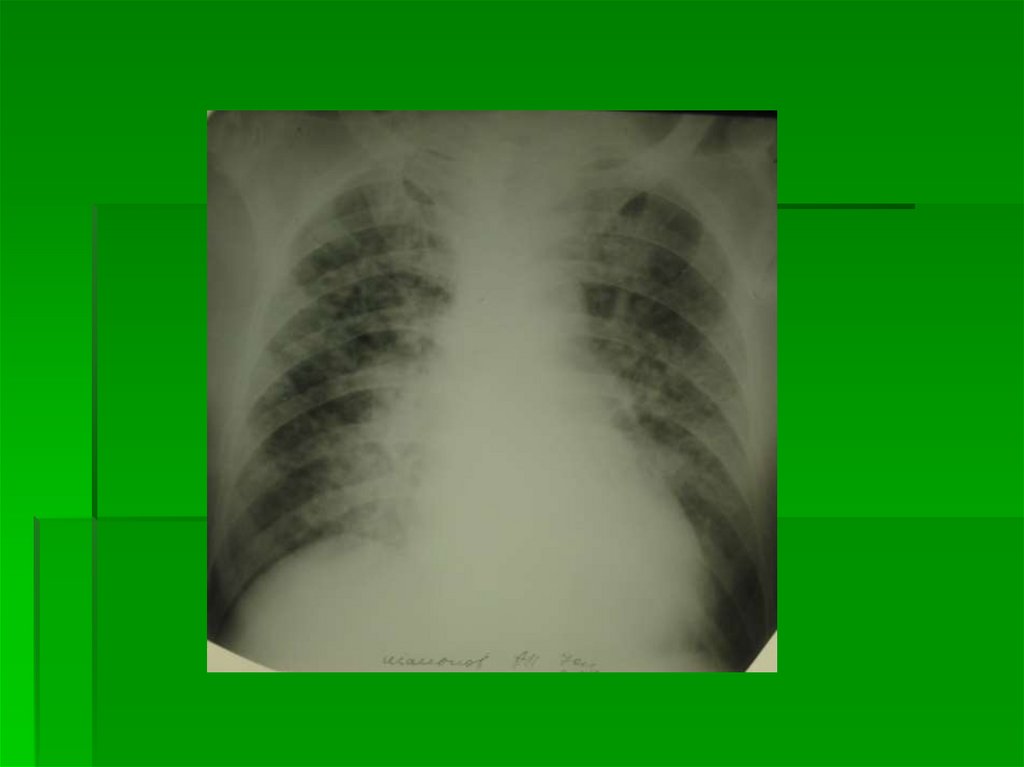

3 степень

Интерстициальный отек

легких

Выход жидкой части крови за пределы

сосудистого русла в интерстициальную

легочную ткань

Корни легких неструктурны,

гомогенизированы, однородны

На фоне корней легких – сосуды в

ортопроекции практически не

дифференцируются

Дифференцируются в ортопроекции

просветы бронхов с утолщенными стенками

в виде маленькой кольцевидной тени с

нечеткими наружными контурами

22.

Прозрачность легких снижена за счет

обилия элементов легочного рисунка

Легочный рисунок утратил обычную

архитектонику, представлен множеством

очаговоподобных теней (расширенные

сосуды в ортопроекции)

и полигональных теней (отечные

междольковые и межальвеолярные

перегородки в ортогональной и косой

проекциях)

23.

Лимфостаз в виде Линий Керли (Kerley) как

обязательный признак ЛВГ 3

Определяются в латерально-базальных

отделах легких (над синусом) в виде коротких

перегородочных линий L=0,5-2,5 см, широким

основанием прилежащих к грудной стенке

Нежная «волосяная» тень междолевой

плевры (лимфостаз по ходу плевры)